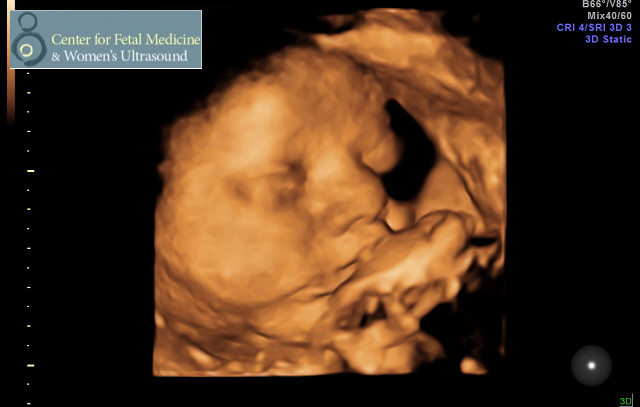

The Joys of (2nd) Pregnancy